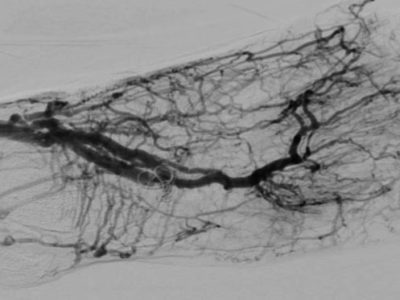

Una nuova pubblicazione del nostro team: Totally Percutaneous Deep Foot Vein Arterialization in a Patient with No-Option Critical Limb Ischemia, Scheduled for Bilateral ...